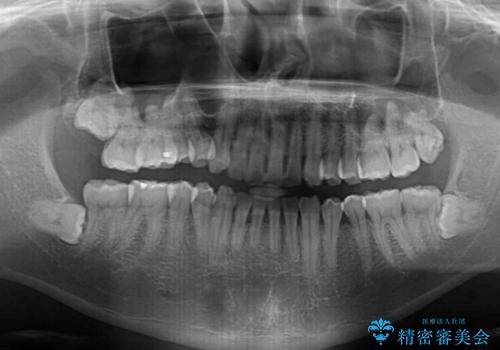

- 以前矯正治療を行ったものの、思い通りの仕上がりではなく、更には後戻りが気になってきたとのことで来院された患者様です。

上顎右側の第一小臼歯が動きにくい歯であり、以前矯正治療を行った際に傾斜した位置のまま終了したことと、それに伴い後戻りで歯列が波打っているようになっていることを大変気にしていらっしゃいました。

咬合平面改善のため、アンカースクリューを多用し、ワイヤー装置にて矯正治療を行うこととしました。